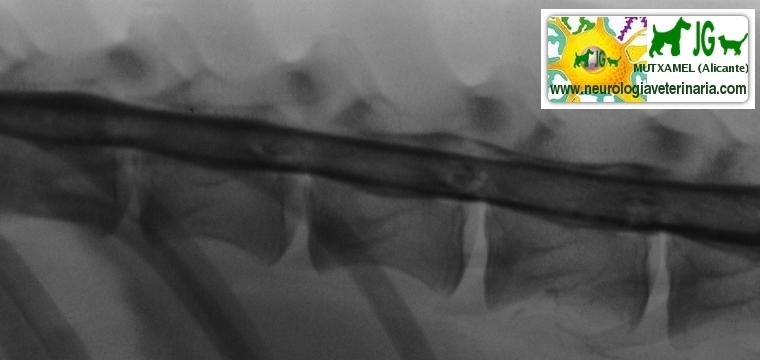

![]() por Juan M. Griñán. Veterinario ![]() comparativa entre una mielografía (mostrando la aguja) y una resonancia magnética, secuencia SE T1w (mostrando donde está el saco dural, sitio para la inyección del contraste). Nótese la extravasación del contraste yodado en la mielografía. | |||||||||